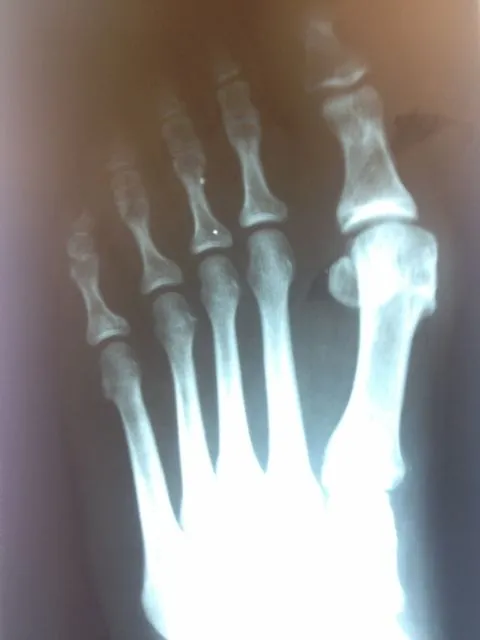

Before and immediately postop S/P bunionectomy

Before and 6 months status post bunionectomy.